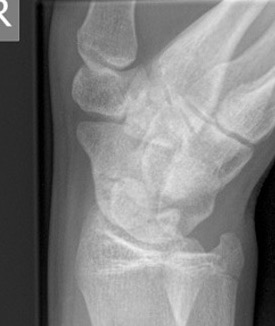

Nonunion with flexion deformity

CT

Indication

- diagnose nonuion

- identify humpback deformity

- plan size and shape of bone graft

Failure of fracture to unite at 3 months on CT scan